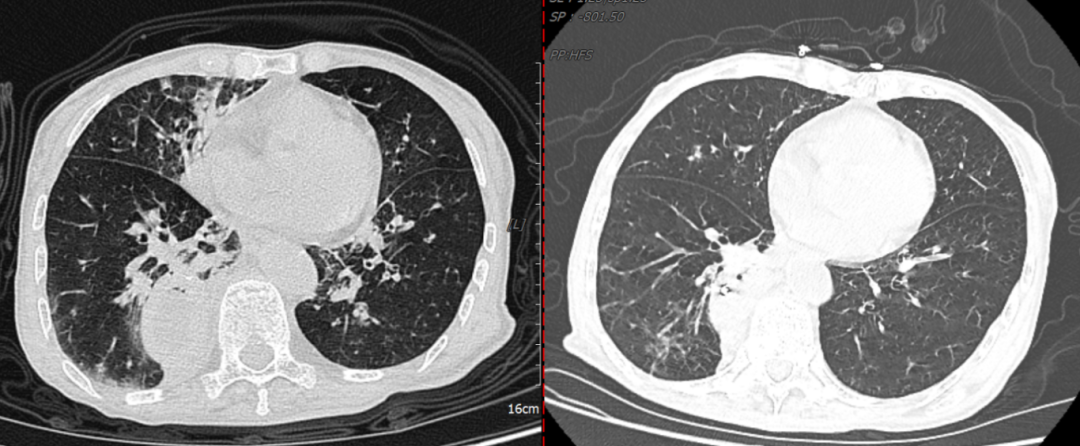

气管覆膜支架完全覆盖瘘口

肺部感染治疗前后对比